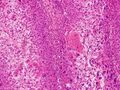

قد يشير التاريخ الطبي والفحص السريري والتصوير الطبي إلى وجود سرطان الخلايا الحرشفية، لكن عادة ما يُحدد التشخيص عن طريق خزعة من أجل التشخيص النسيجي. تُعد صبغة TP63 العلامة النسيجية الرئيسية لسرطان الخلايا الحرشفية. بالإضافة إلى ذلك، تُعد TP63 عامل نسخ أساسي لتحديد هوية الخلايا الحرشفية.[18]

التصنيف

يمكن اعتبار السرطان عائلة كبيرة للغاية من الأمراض الخبيثة، ومتمايزة بشكل استثنائي، حيث تشكل سرطانات الخلايا الحرشفية واحدة من أكبر المجموعات الفرعية.[19][20][21] يُعتقد أن جميع آفات سرطان الخلايا الحرشفية تبدأ من خلال الانقسام المتكرر وغير المنضبط لخلايا جذعية سرطانية من السلالة أو الخصائص الظهارية.[citation needed] تنشأ سرطانات الخلايا الحرشفية من الخلايا الحرشفية، وهي خلايا مسطحة تبطن مناطق عديدة من الجسم، بعضها من الخلايا الكيراتينية. يُسبب تراكم هذه الخلايا السرطانية بؤرة مجهرية من الخلايا الشاذة التي تكون، في البداية على الأقل، محصورة موضعياً داخل النسيج المحدد الذي كانت تتواجد فيه الخلية السلفية. تُسمى هذه الحالة سرطان الخلايا الحرشفية الموضعي، وتُشخص عندما لا يكون الورم قد اخترق الغشاء القاعدي أو أي بنية فاصلة أخرى للتوغل في الأنسجة المجاورة. بمجرد نمو الآفة وتطورها إلى الحد الذي تخترق فيه وتتسلل إلى الأنسجة المجاورة، يُشار إليها باسم "سرطان الخلايا الحرشفية المتوغل". بمجرد أن يصبح السرطان متوغلاً، يمكن أن ينتشر إلى أعضاء أخرى ويسبب تكوين ورم ثانوي.[citation needed]